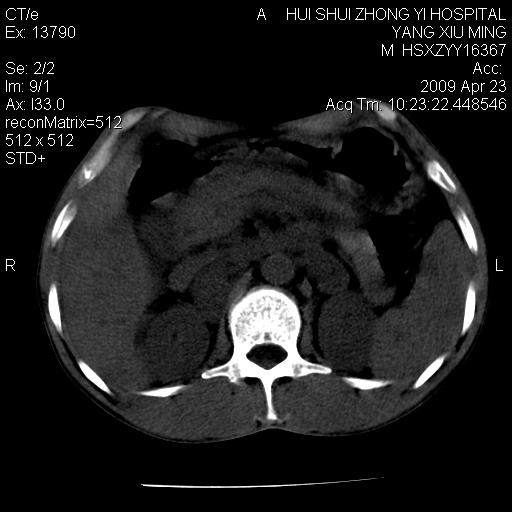

上腹部疼痛一月,呕吐10天,发现左侧颈部包快10天 胸部cr片未见明显异常。

腹膜后淋巴结增大,转移、淋巴瘤?胰腺增大,胰腺炎?占位?颈部考虑增大淋巴结。建议腹部增强扫描。

连最基本的ct值都没有测        腹部的窗宽窗位太大了     影响诊断

黑!广泛淋巴结肿大不符合胰腺癌转移。胰腺周围淋巴结肿大致使胰腺看起来大。考虑淋巴瘤可能大。